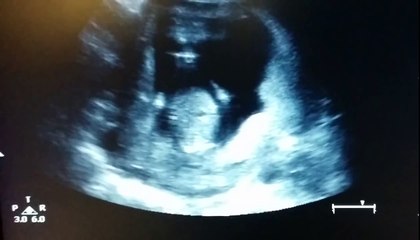

This is the moment a shocked man was told he was about to become a dad for the fifth time - a day before a scheduled vasectomy.br br Brittney McHenry, 37, and her husband Ryan, 39, are parents to four kids —Jack, six, and four-year-old triplets Parker, Tucker, and Madison.br br All were conceived with medical help and, believing their family was complete, Ryan booked a vasectomy.br br But the day before his appointment, Brittney had a gut feeling and took a pregnancy test — only to find out she was unexpectedly expecting.br br Despite the shocking news, Ryan still went ahead with the procedure and the couple is now thrilled to be welcoming their fifth child.br br Brittney, from Utah said: “I was devastated and he was shocked. We’d never been able to get pregnant on our own before.